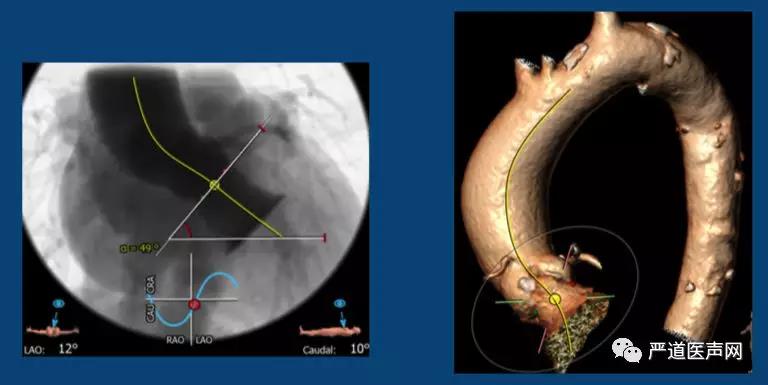

2.患者主动脉弓夹角49°,要求输送系统具有较好的通过性,以免损伤主动脉,并顺利通过主动脉弓